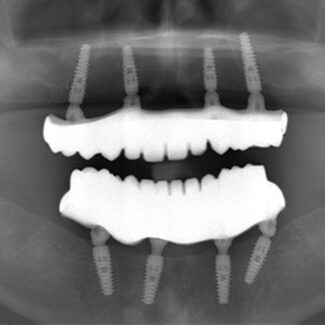

Before and After

SEE OUR RESULTS